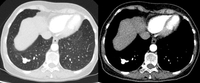

PET CT scan with 18-fluorodeoxyglucose (18-FDG) showing a low uptake in a semi-solid right upper lobe posterior lesion. Surgical resection confirmed adenocarcinoma with primarily lepidic pattern

From the collection of Dr George Tsaknis, MD, PhD, FRCP(London), MRQA, MAcadMEd, PGCert; used with permission